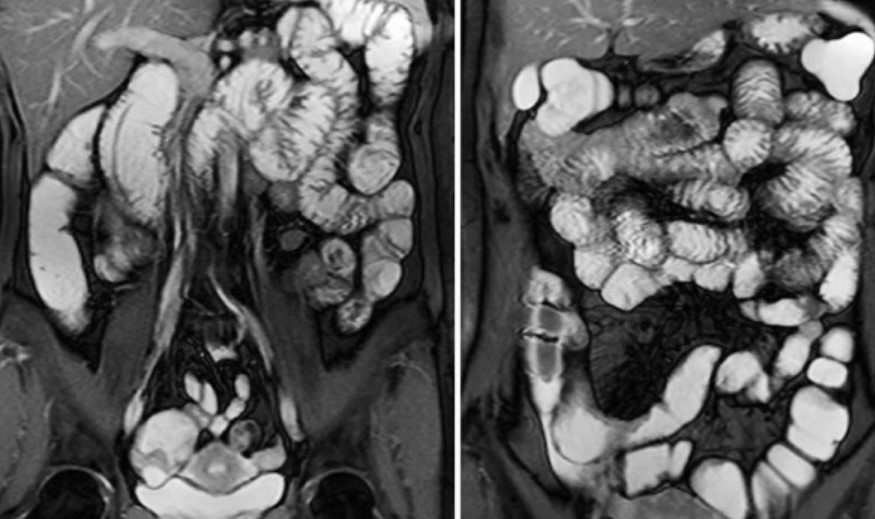

Вид внутренних органов живота при МР-исследовании с двойным контрастированием

Магнитно-резонансная томография может быть выполнена с использованием разных последовательностей и вариантов усиления. При подозрении на патологический процесс в слизистой оболочке подвздошной, тощей или двенадцатиперстной кишки проводят исследование с двойным контрастированием (гидро-МРТ, энтерография). Вещество с парамагнетическими свойствами вводят перорально и внутривенно. После расправления складок и “подсвечивания” сосудов выполняют сканирование брюшной полости.